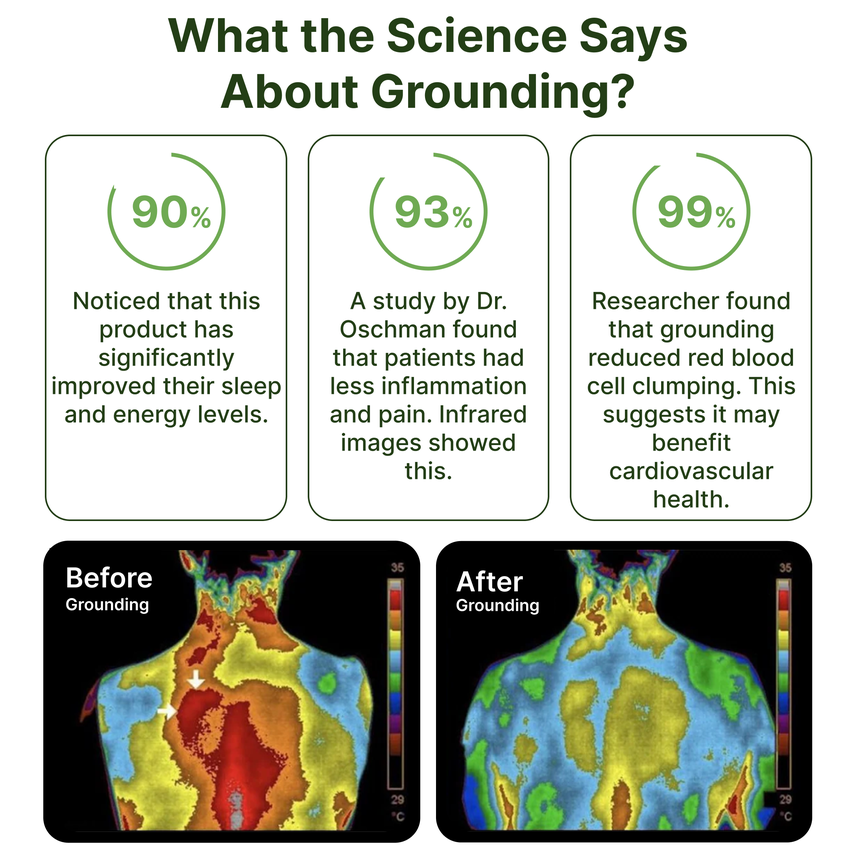

Connecting with the underestimated natural force beneath our feet, grounding establishes a harmonious link to the Earth, fostering equilibrium and nourishment at profound levels within ourselves. This process not only alleviates inflammation, pain, stress, and fatigue but also nurtures overall well-being.

Grounding stands as a holistic breakthrough in health with ever-growing research to back its benefits. Grounding presents a straightforward yet profound lifestyle enhancement that often unfolds with remarkable healing effects.

A prime illustration lies in its impact on chronic inflammation, a crucial factor in various aging-related disorders like arthritis and autoimmune conditions, as well as mental health challenges such as chronic stress and anxiety. Grounding efficiently addresses inflammation, swiftly alleviating the associated pain.

Essentially, grounding involves restoring a crucial energy connection to the Earth, a connection that gradually wanes due to our modern lifestyle choices. Many adults are burdened by persistent pain and compromised health due to this disconnection. Upon reestablishing this vital link, people report benefits to reduction in pain and use of medications and improved sleep, contributing to a more comprehensive and holistic sense of well-being.